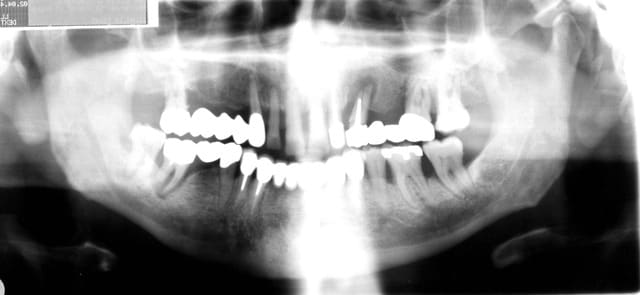

P.S: désolé pour la mauvaise qualité des pano

Opt lag12 p2a1hr - Eugenol

D'après moi, un bilan long cône est indispensable.

Un scanner aussi, pour prévoir le comblement.